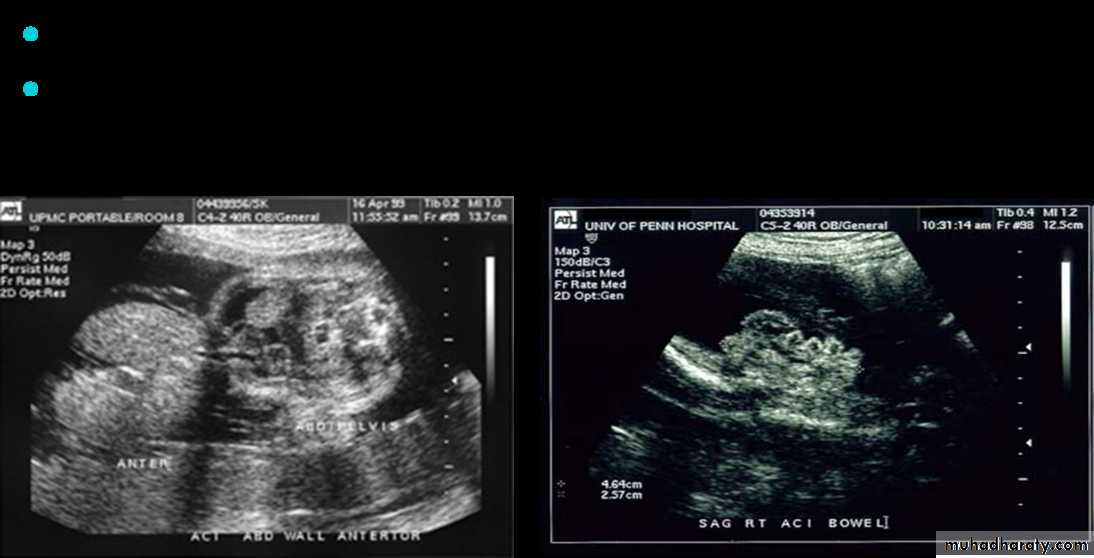

Prenatal Diagnosis

If the Omphalocele is larger than 5 cm delivary should be through CS ,while if less than 5 cm could be with normal vaginal delivaryInitial Management